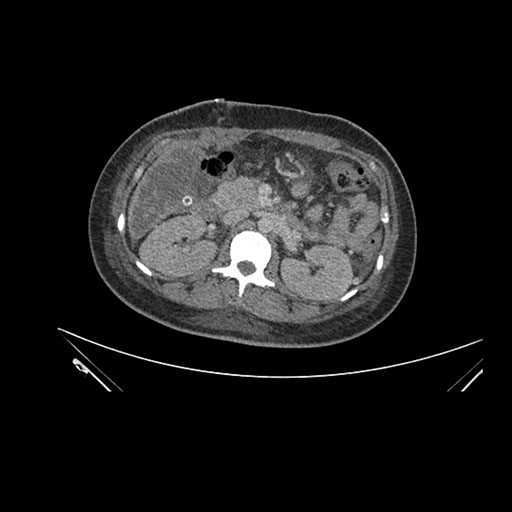

Axial Venous

Imaging analysis

Based on initial findings, which issue(s) would you be most concerned about?